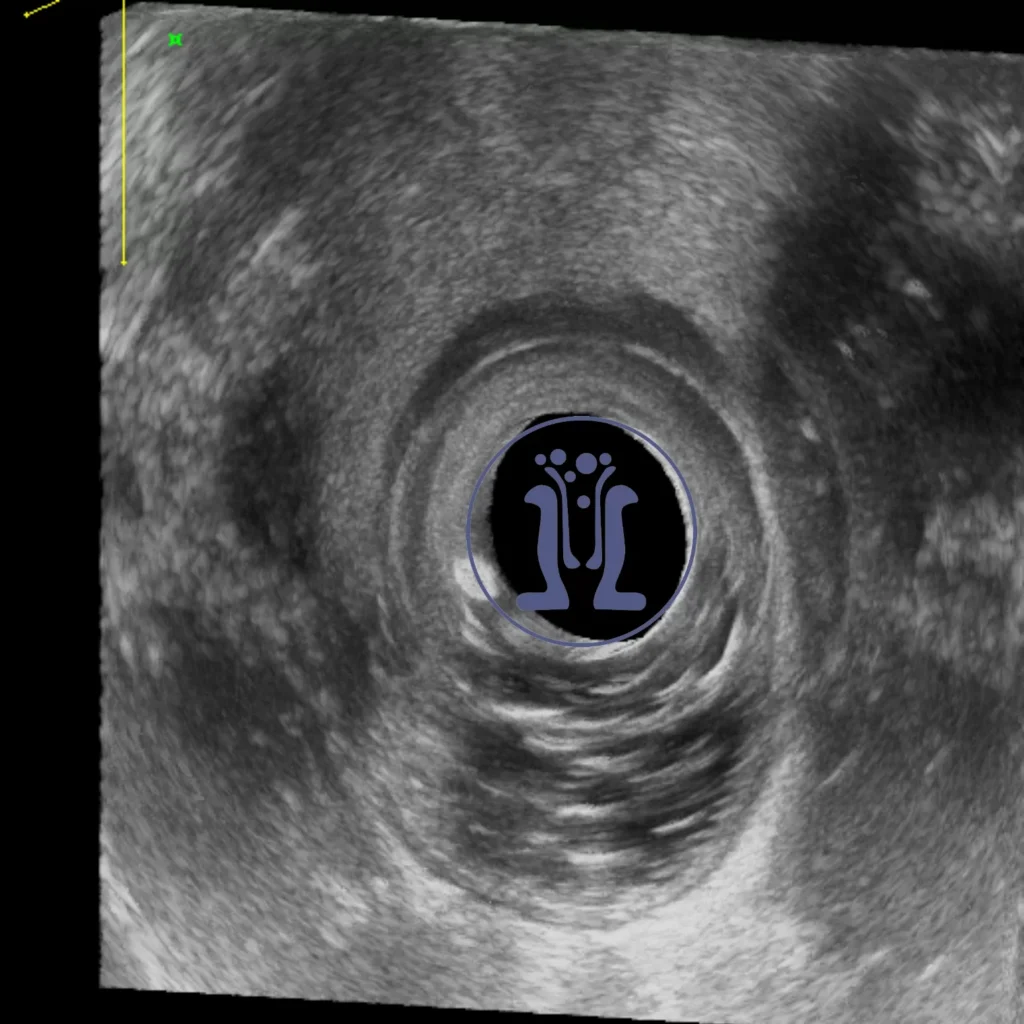

Το ενδοπρωκτικό υπερηχογράφημα δείχνει μία κύστη στο οπίσθιο άνω τεταρτημόριο του πρωκτικού σωλήνα με χαρακτήρες οπισθοορθικής κύστης. Η οπίσθοορθική κύστη είναι μία κύστη που αναπτύσσεται πίσω από το ορθού και πιθανότατα προκαλείται από παραμονή και περαιτέρω ανάπτυξη εμβρυικού υπολείμματος.